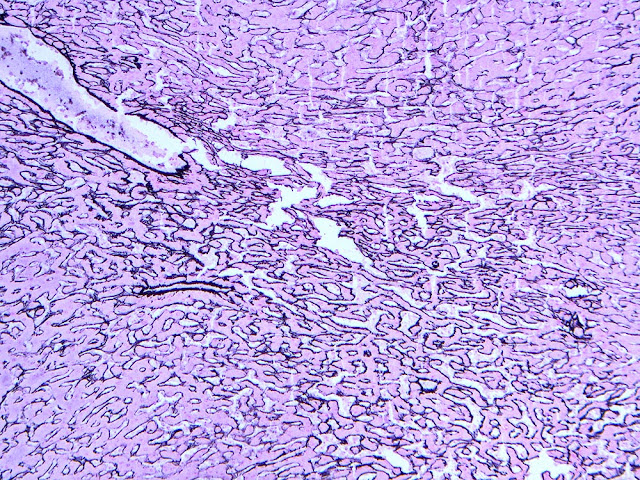

The explant showed a nodular liver with areas of sinusoidal dilatation, and occasional incomplete septae, but no evidence of cirrhosis. Rare florid ducts of PBC are present but there is mild ductopenia that came down to approximately just 20% of the terminal bile ducts; the larger bile ducts appear normal as are most of the small/terminal bile ducts. Several small portal tracts however have increased portal and occasionally periportal fibrosis and no visible portal veins. The larger portal tracts often have small portal veins when compared with the corresponding hepatic artery or bile duct, with thickening of the veins walls (obliterative portal venopathy). Reticulin stain demonstrates nodularity not bordered by fibrous septae, the edge of the nodules having compressed reticulin fibers (NRH). Sections from the hilum demonstrate major but non-occlusive portal vein thrombus.

Non-cirrhotic portal hypertension from a combination of nodular regenerative hyperplasia (NRH), portal vein thrombosis, and obliterative portal venopathy (OPV) in a patient transplanted for Primary Biliary Cirrhosis